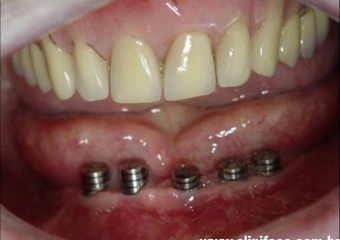

Implantes com cicatrizadores